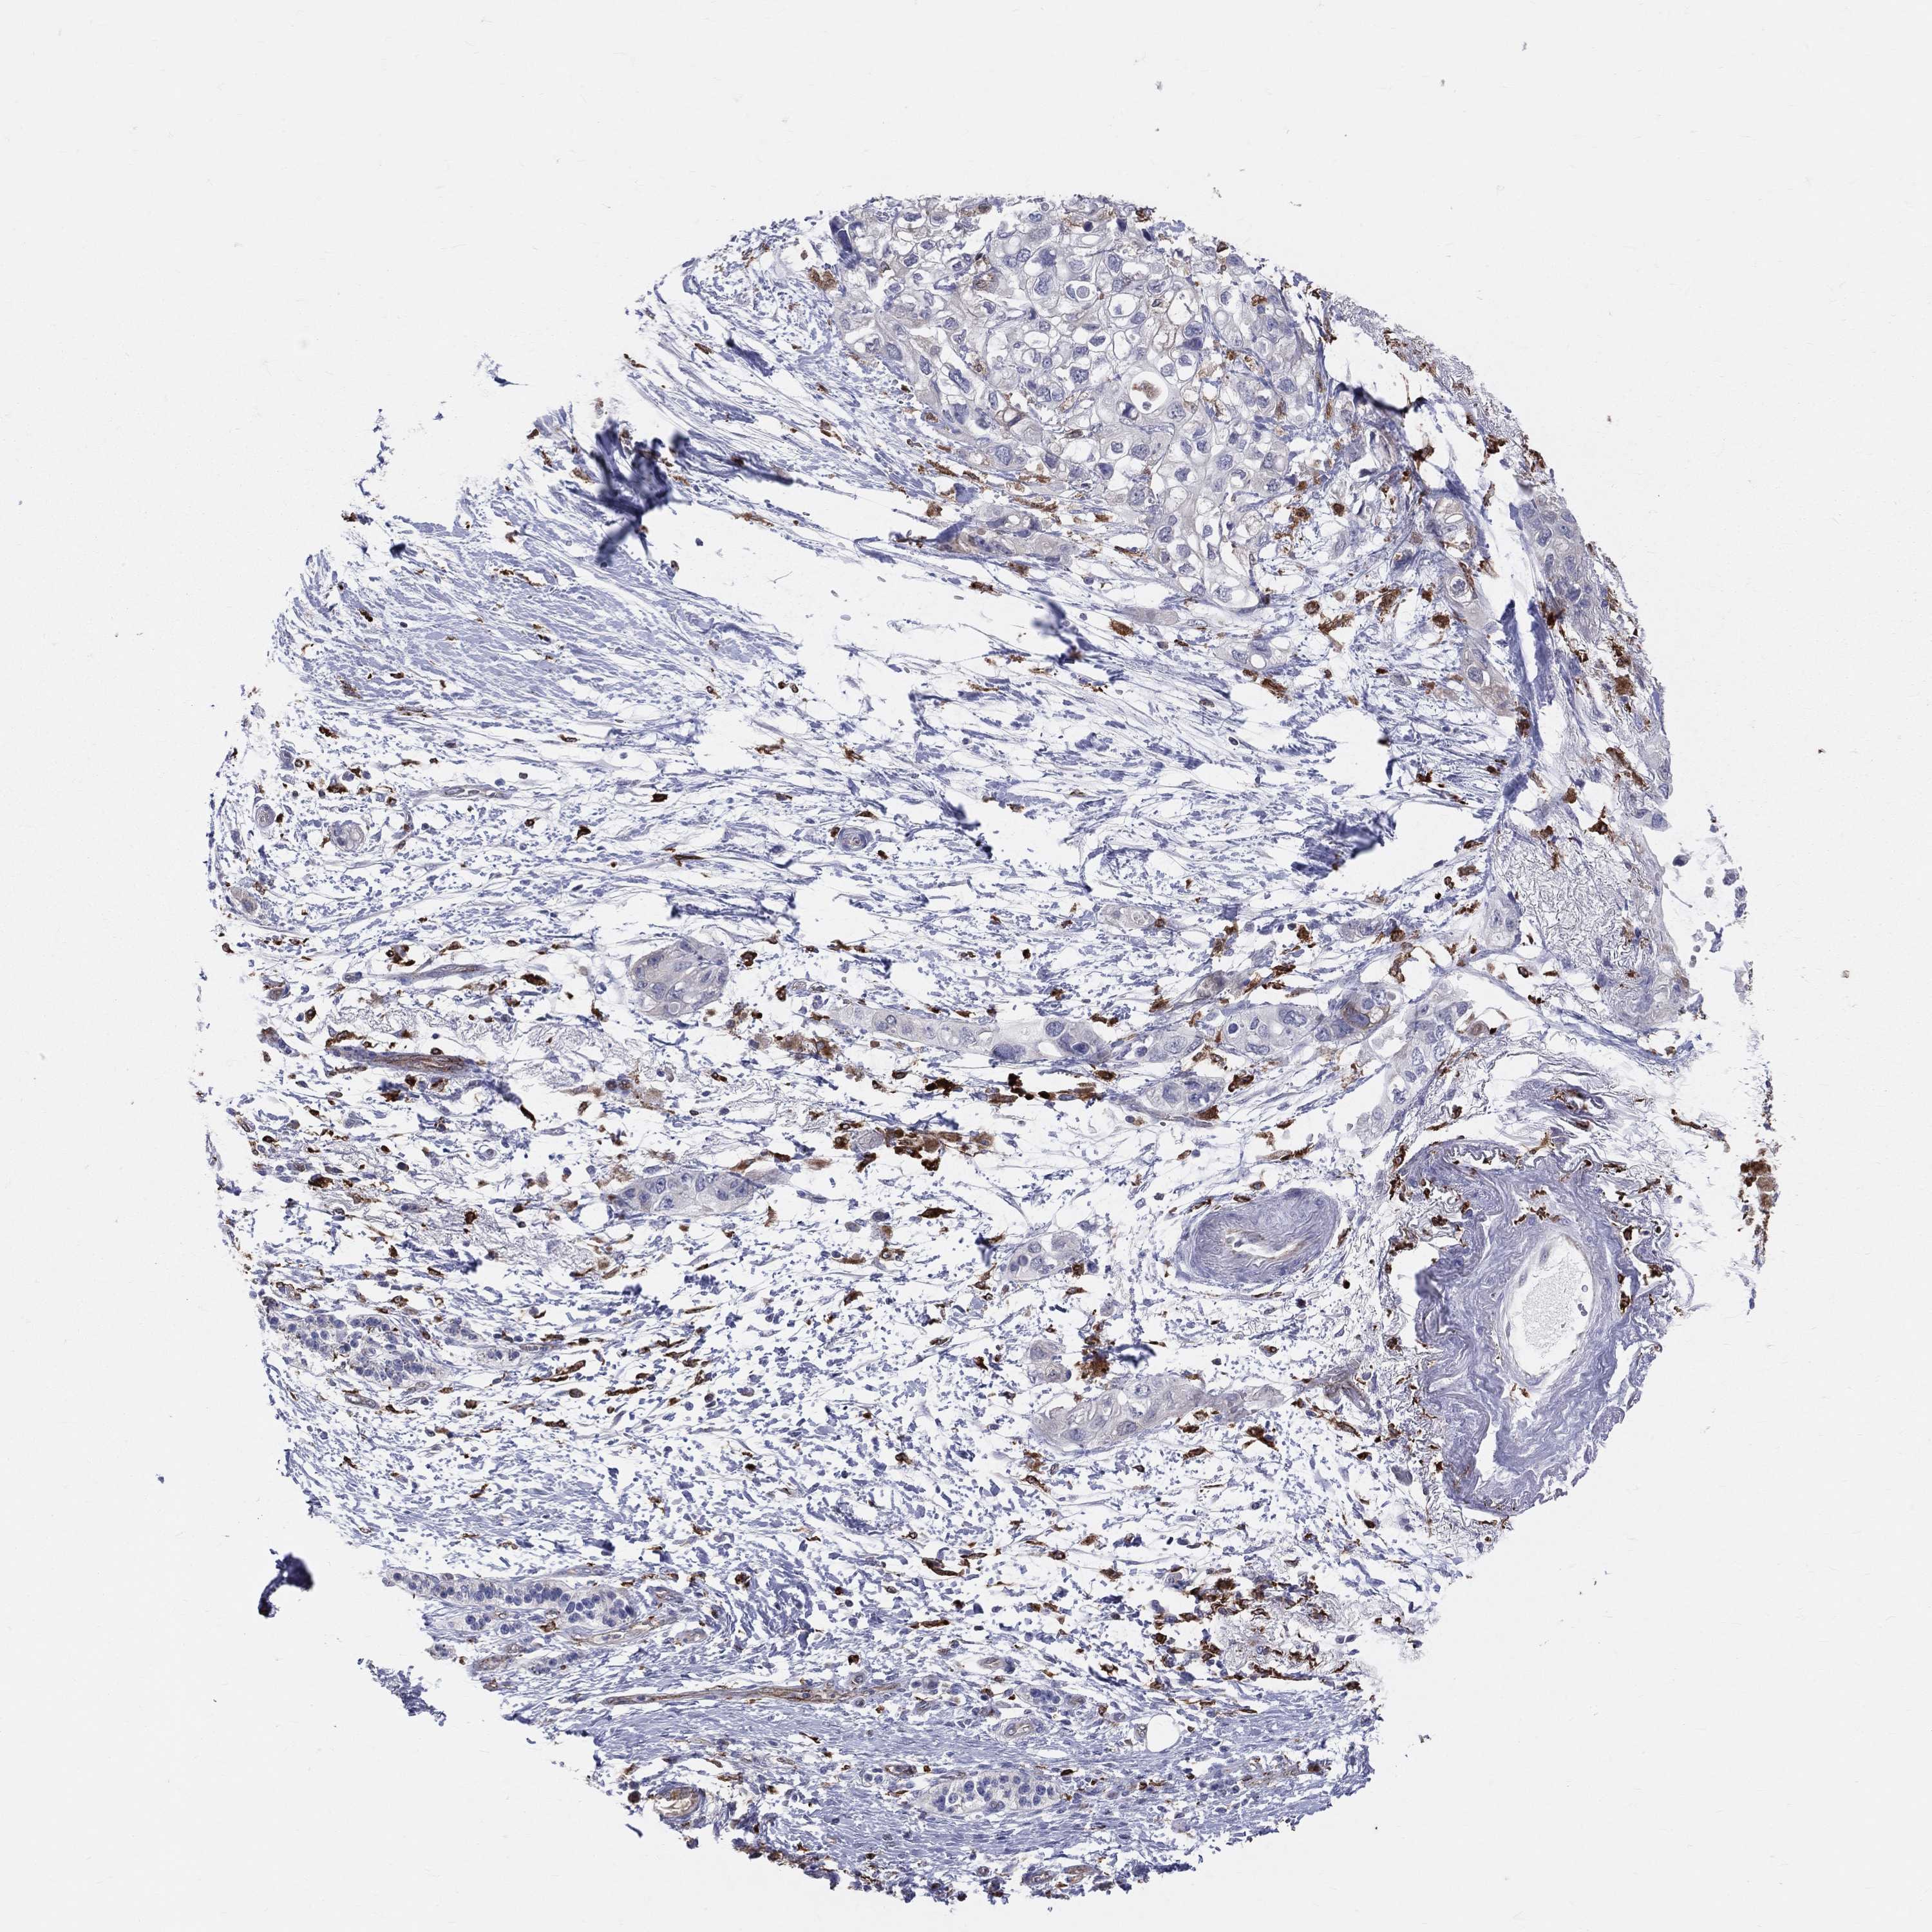

PANCREATIC CANCER - Protein expressioni

A mouse-over function shows sample information and annotation data. Click on an image to view it in a full screen mode. Samples can be filtered based on level of antibody staining by selecting one or several of the following categories: high, medium, low and not detected. The assay and annotation is described here.

Note that samples used for immunohistochemistry by the Human Protein Atlas do not correspond to samples in the TCGA dataset.

Antibody stainingi

Antibody staining in the annotated cell types in the current human tissue is reported as not detected, low, medium, or high, based on conventional immunohistochemistry profiling in selected tissues. This score is based on the combination of the staining intensity and fraction of stained cells.

Each image is clickable and will lead to virtual microscopy that enables deeper exploration of all samples and also displays staining intensity scores, fraction scores and subcellular localization as well as patient and tissue information for each sample.

Antibody HPA010592

Antibody CAB002506

Antibody CAB079994

Staining

High

Medium

Low

Not detected

Intensity

Strong

Moderate

Weak

Negative

Quantity

>75%

75%-25%

<25%

None

Location

Nuclear

Cytoplasmic/membranous

Cytoplasmic/membranous,nuclear

Adenocarcinoma, NOS

Adenocarcinoma, metastatic, NOS